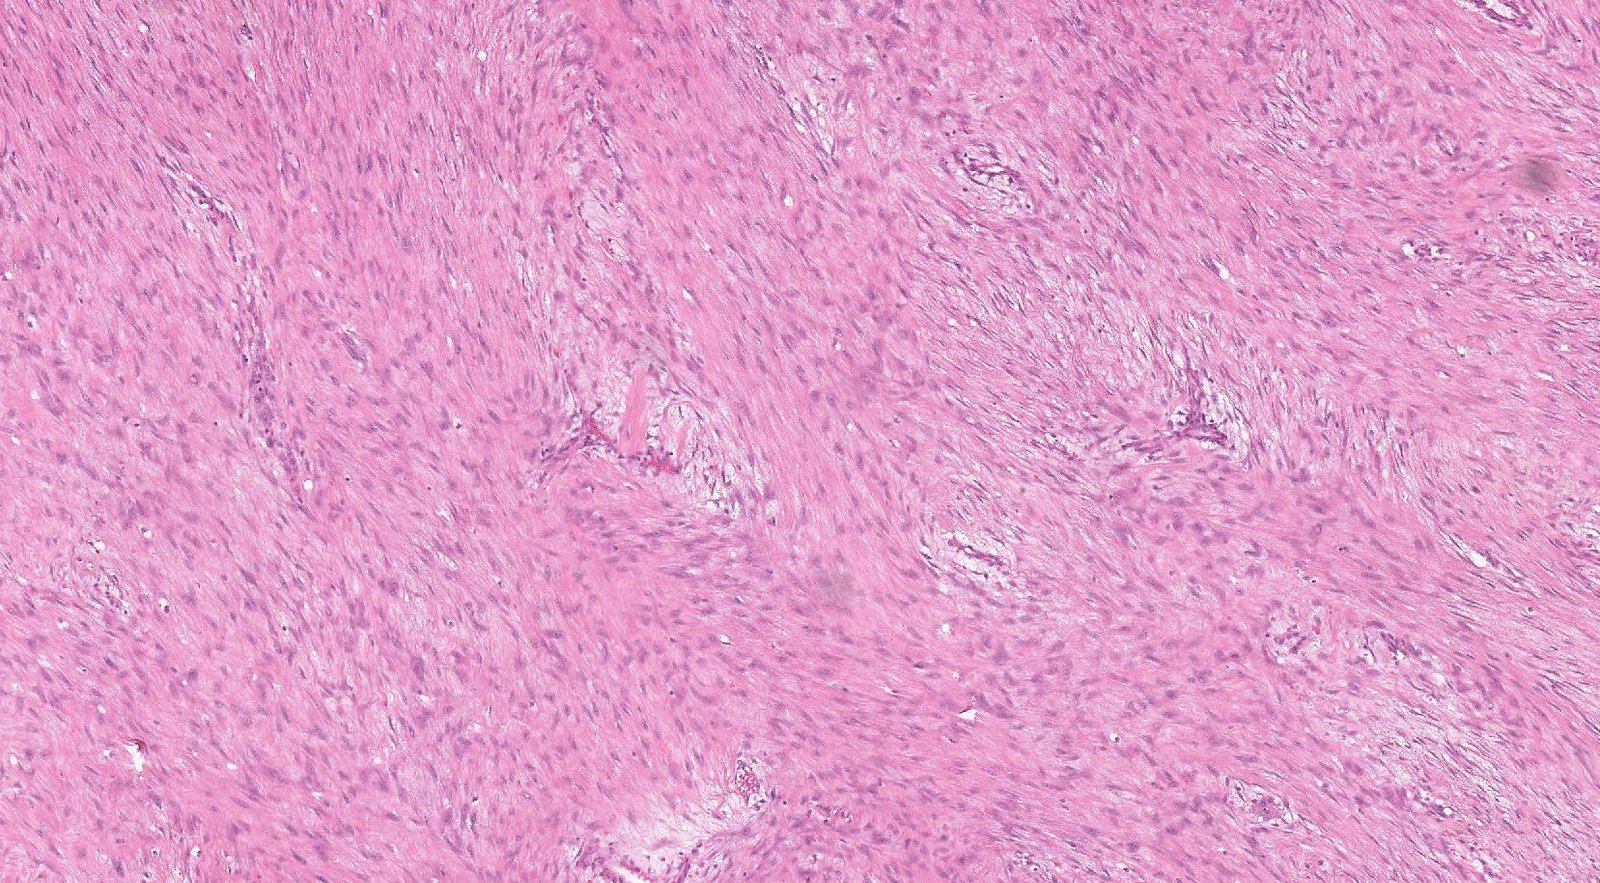

Case: AbdominalMass2

Final Diagnosis: